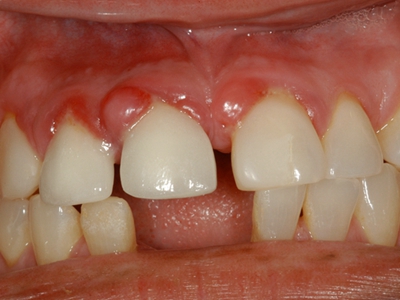

牙龈炎是发生于牙龈组织的炎症,患者可出现牙龈出血伴肿胀、发红、正常形态改变和偶尔不适等症状。本病主要由口腔卫生状况差导致,包括口腔不洁、牙菌斑等,诊断依据临床检查,治疗包括专业牙齿清洁和加强家庭口腔卫生。

牙龈炎可先引起牙齿与牙龈之间的沟(龈沟)加深,然后牙龈充血,炎症围绕一个或多个牙齿,伴牙龈乳头肿胀和易出血。一般无痛,可自行消退,也可维持轻度炎症数年。